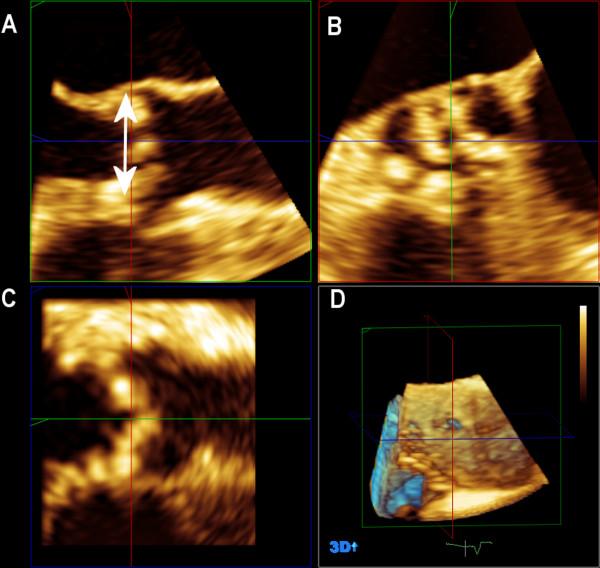

Aortic stenosis (AS) is a relevant common valve disorder. Severe AS and symptoms and/or left ventricular dysfunction (EF <50%) have the indication for aortic valve replacement (AVR). Majority of the patients with AS are elderly often with co-morbidities and generally have high preoperative risk. Transcatheter aortic valve implantation (TAVI) is offered in this group. Four different sizes of Corevalve prosthesis are available. Correct measurement of aortic size prior to TAVI is of great important to choose the right prosthesis size to avoid among others paravalvular leak or prosthesis patient mismatch.Aim of the study is to assess the aortic annulus diameter in patients undergoing TAVI by biplane (BP) mode using transesophageal echocardiography (TEE) and compare it to two-dimensional (2D) transthoracic echocardiography (TTE) and 2DTEE using three-dimensional (3D) TEE as reference method.

主动脉瓣狭窄(AS)是一种常见的重要瓣膜疾病。重度AS以及症状和/或左心室功能障碍(射血分数<50%)有主动脉瓣置换术(AVR)的指征。大多数AS患者为老年人,常伴有合并症,术前风险一般较高。该类患者可采用经导管主动脉瓣植入术(TAVI)。有四种不同尺寸的Corevalve人工瓣膜可供使用。在TAVI术前正确测量主动脉大小对于选择合适的人工瓣膜尺寸非常重要,以避免出现瓣周漏或人工瓣膜与患者不匹配等问题。本研究的目的是通过经食管超声心动图(TEE)的双平面(BP)模式评估接受TAVI治疗患者的主动脉瓣环直径,并将其与二维(2D)经胸超声心动图(TTE)以及以三维(3D)TEE作为参考方法的2DTEE进行比较。